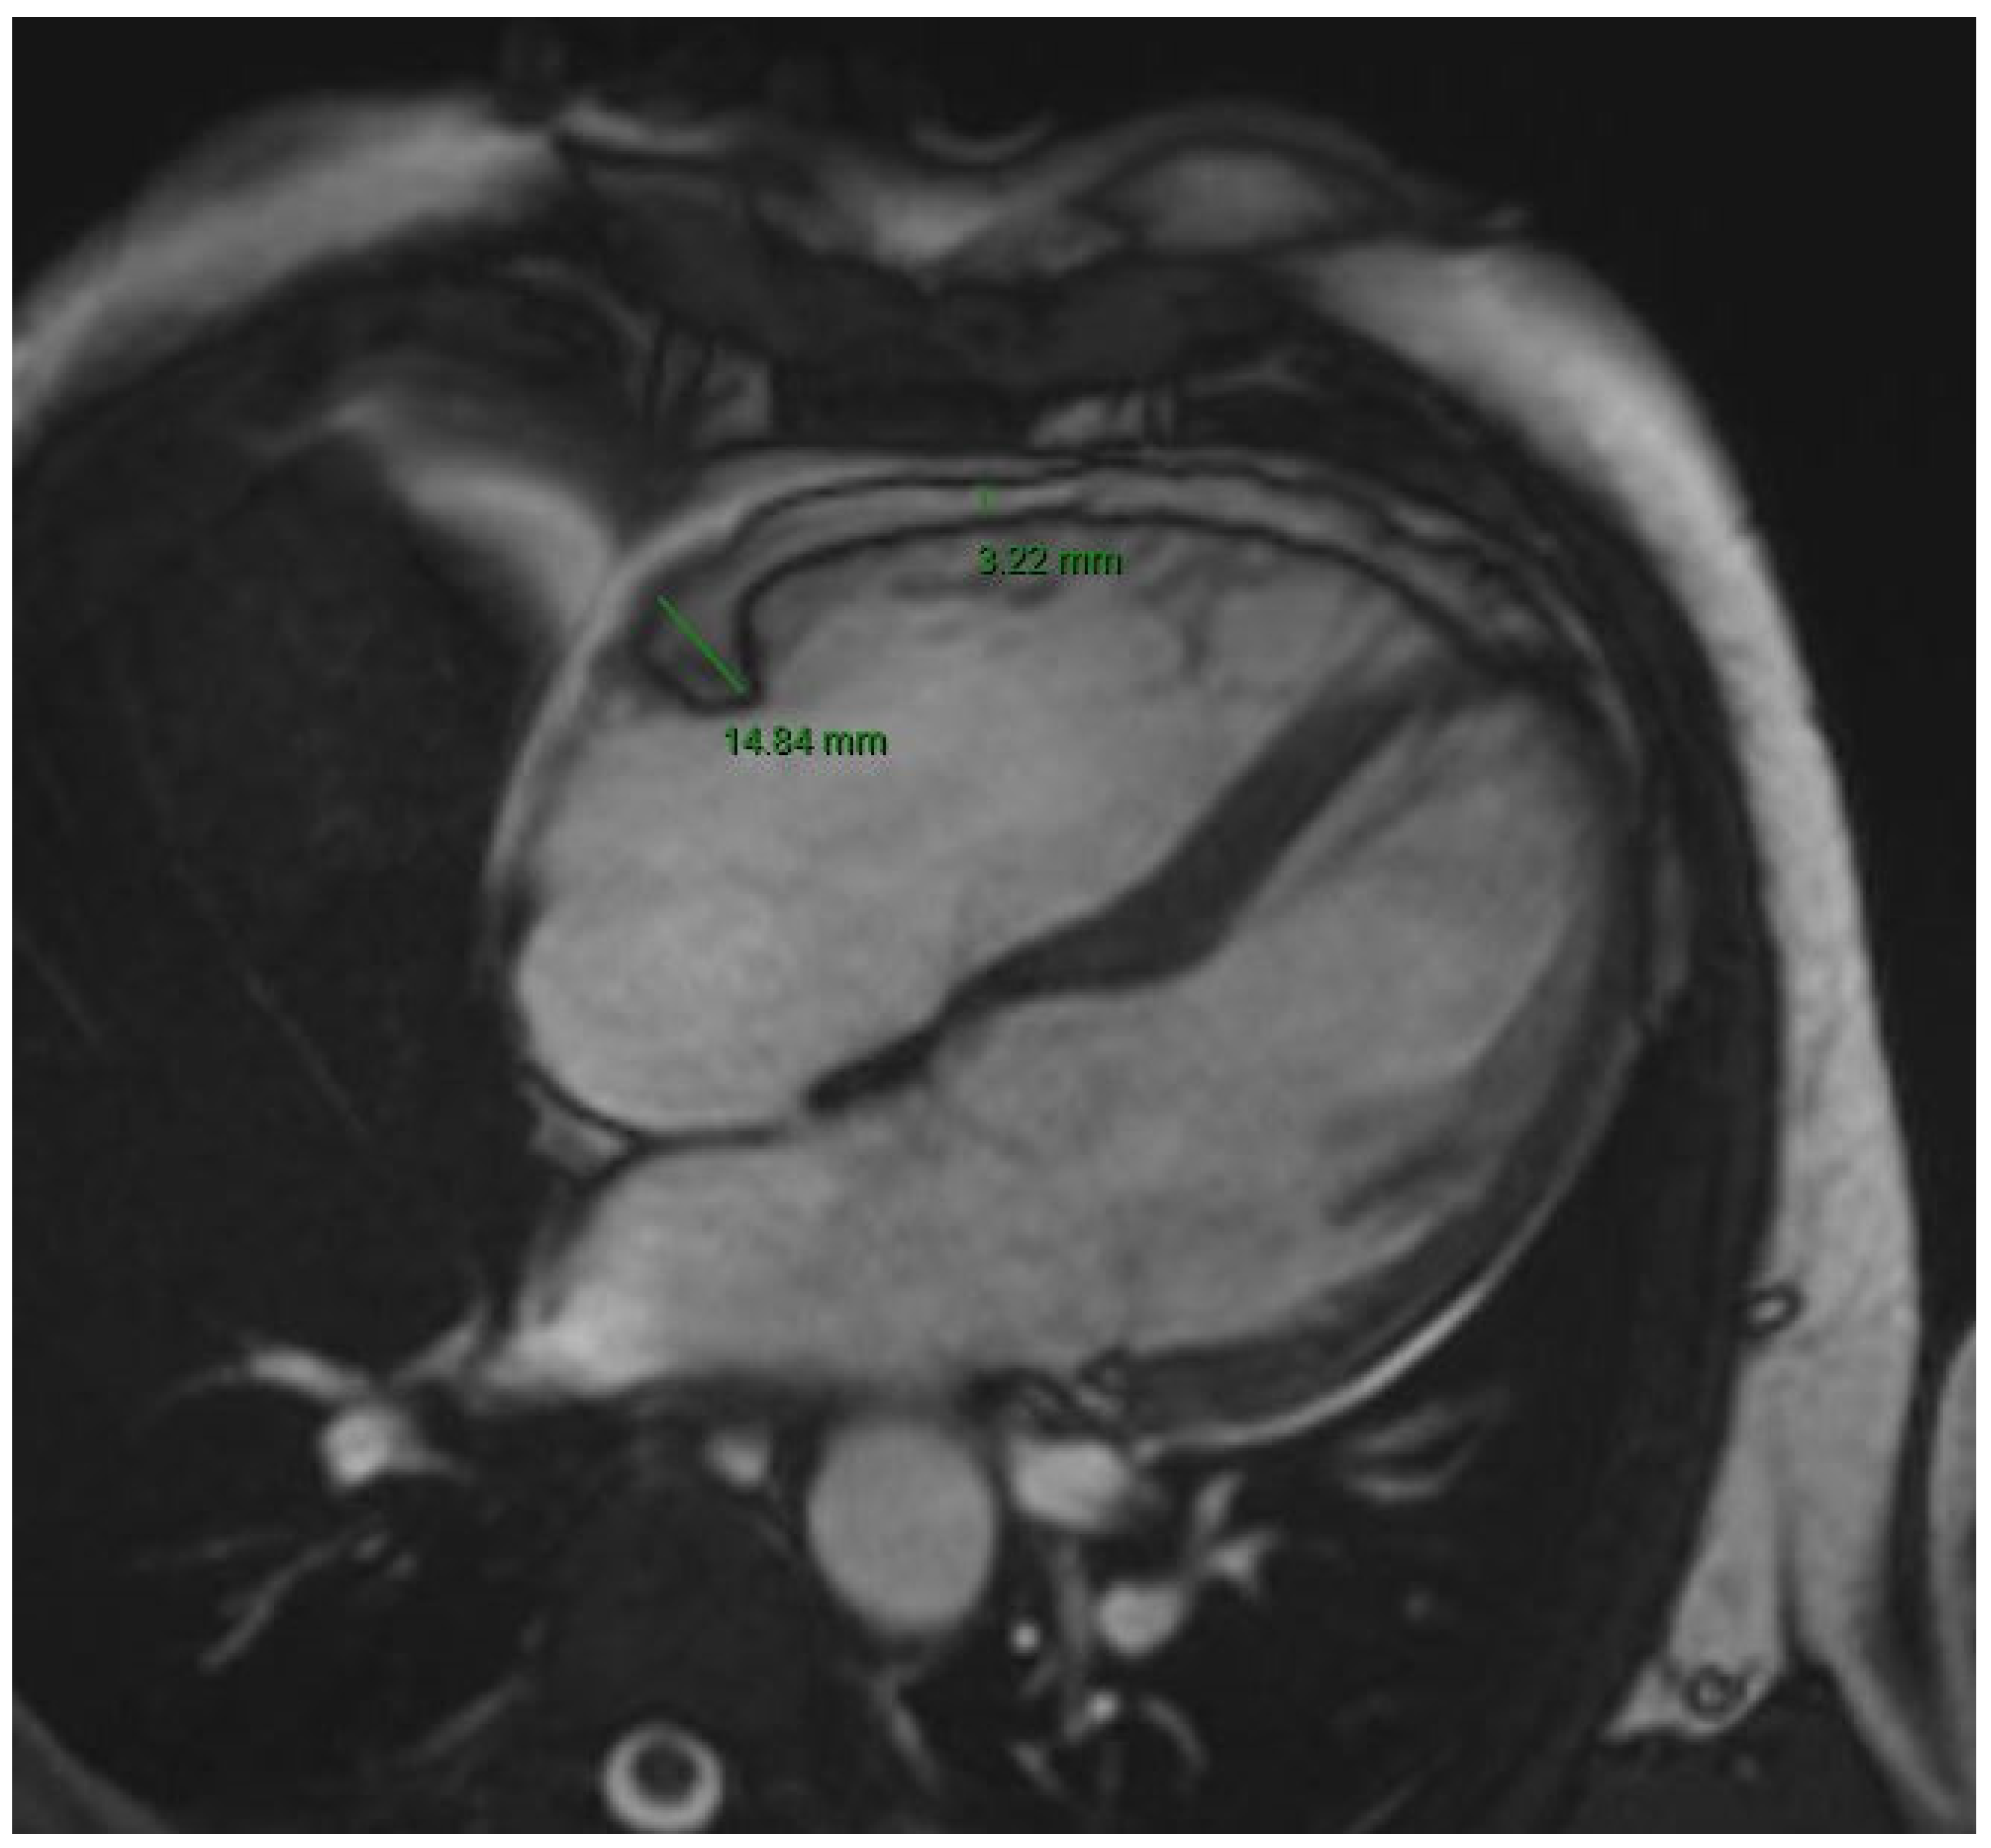

| RA EAT (mm) | 4.0 [3.3–4.7] | 4.0 [3.2–4.4] | 4.4 [3.9–5.0] | 0.02 |

| LA EAT (mm) | 4.4 [3.6–5.5] | 4.0 [3.4–5.2] | 5.0 [4.2–6.0] | <0.01 |

| LA EAT | 1.61 | 1.14–2.28 | 0.01 | 1.91 | 1.08–3.40 | 0.01 |